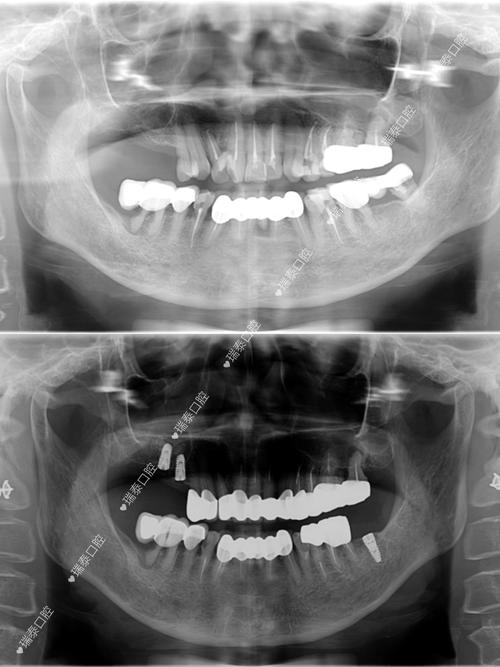

- 影像学检查: 必须拍摄CBCT,精确评估牙槽骨的高度、宽度、密度,以及重要的解剖结构(如下牙槽神经管、上颌窦位置)。

- 取模/口扫: 制作研究模型或进行数字化口扫,用于手术导板设计和最终修复方案。